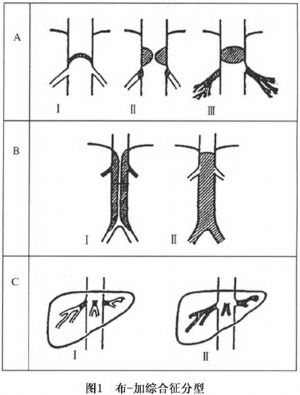

對於肝靜脈和(或)肝段下腔靜脈阻塞的類型、部位及形態許多人作了較爲詳盡的觀察。按照阻塞的性質、位置、範圍和程度予以分型,對於正確地治療和選擇手術方式是非常重要的。許多學者提出了各種分型意見。其中以Hirooka分型最詳細,具體闡明瞭下腔靜脈、肝靜脈的病理特性、部位和相互關係,同時發現膜狀阻塞有薄膜和厚膜的不同。

由於Hirooka分型過於繁雜,不便實用。汪忠鎬綜合各種分類方法,根據下腔靜脈阻塞的特性、肝靜脈受累的情況,從便於手術選擇的角度將本病分爲3種類型(圖1)。

Ⅰ型:下腔靜脈隔膜爲主的侷限性狹窄或阻塞型(約佔57%)。此型系高位下腔靜脈隔膜樣阻塞或纖維性阻塞,肝靜脈未被累及,但是,肝靜脈開口位於下腔靜脈阻塞的遠側。因此,除下腔靜脈有阻塞外,肝靜脈迴流亦受阻。此型在日本相當多見。下腔靜脈阻塞的遠側,血流淤滯,可繼發血栓形成。若血栓延伸,即可堵塞肝靜脈開口和主幹。

Ⅱ型:瀰漫性狹窄或阻塞型(約佔38%)。下腔靜脈瀰漫性狹窄或阻塞,肝後段下腔靜脈節段性或瀰漫性阻塞,合併左肝靜脈或右肝靜脈閉塞,甚至肝靜脈主幹全部閉塞。亞洲和遠東地區所見者多屬此型。

Ⅲ型:肝靜脈阻塞型(約佔5%)。肝靜脈主幹或開口阻塞,下腔靜脈通暢。此型多發生在西歐和北美地區。常表現爲肝靜脈血栓形形形成或血栓性靜脈炎。有學者觀察到,隨着病程的延長,肝靜脈出口附近的下腔靜脈繼發血栓形成。

目前世界上無統一的分型,Hirooka根據下腔靜脈、肝靜脈的病理特性、部位和相互關係分爲Ⅰa、Ⅰb、Ⅰc、Ⅱa、Ⅱb、Ⅲ、Ⅳ、Ⅴ、Ⅵ、Ⅶ型,此分型法雖最詳細但過於繁瑣;孫建民綜合各類分類法,根據下腔靜脈阻塞的特性、肝靜脈受累的情況,將Hirooka分型簡化爲4型:

Ⅰ型:下腔靜脈膜狀阻塞,部分性或完全性,肝靜脈主幹通暢,或一支通暢,一支閉塞(即HirookaⅠ、Ⅱ型)。

Ⅱ型:兩側肝靜脈主幹開口處閉塞,腔靜脈無病變(Hirooka Ⅶ型)。

Ⅲ型:下腔靜脈纖維性狹窄,二側肝靜脈主幹通暢(Hirooka Ⅲ型)。

Ⅳ型:下腔靜脈狹窄,血栓形成閉塞(Hirooka Ⅳ、Ⅴ、Ⅵ型)。

冷希聖從臨牀及手術治療出發,分爲4型:

Ⅰ型:下腔靜脈膜狀阻塞(厚度0.5cm以下),肝靜脈主幹至少有一支通暢。

Ⅱ型:下腔靜脈非膜狀阻塞(厚度0.5~5cm),肝靜脈主幹至少有一支通暢。

Ⅲ型:下腔靜脈廣泛狹窄閉塞(長度>5cm)或膜狀阻塞合併肝靜脈主要分支完全阻塞。